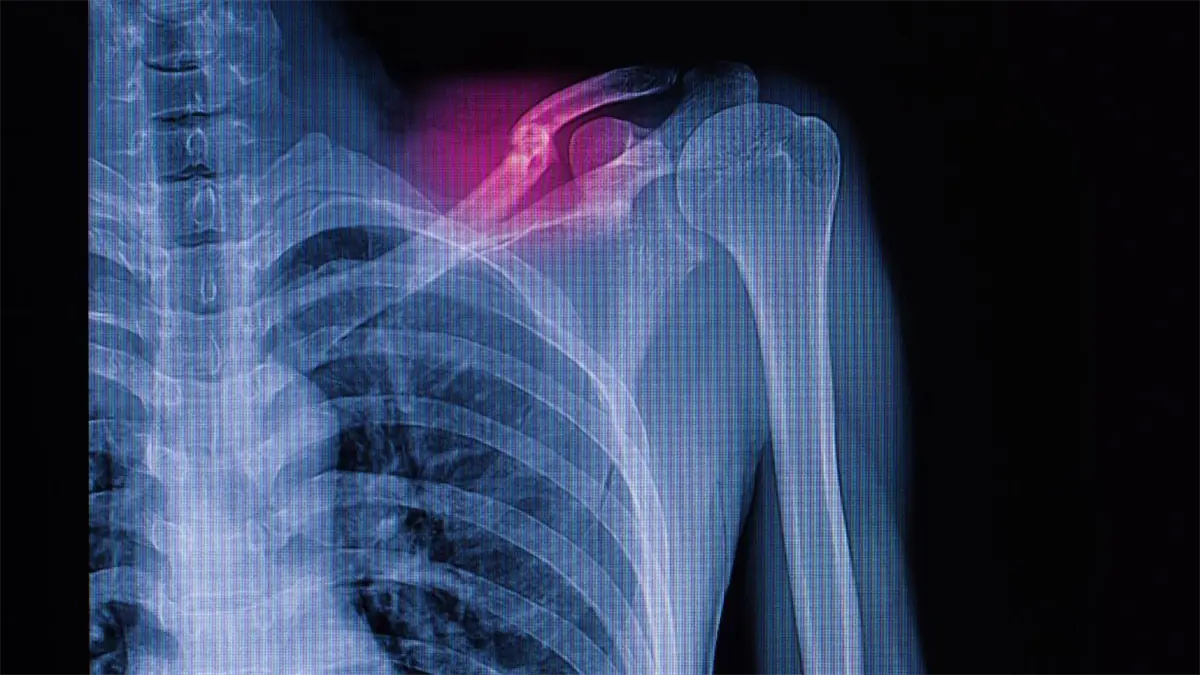

Hong Kong desarrolla nanocemento óseo para tratamiento de fracturas y reparación rápida

Hong Kong.– Un equipo de la Facultad de Medicina LKS de la Universidad de Hong Kong (HKUMed) ha desarrollado un innovador material de fosfato de calcio elástico, conocido como «cemento óseo nano«, que imita la estructura del hueso humano y promete transformar el tratamiento de fracturas.

Este avance ofrece una alternativa a los injertos óseos tradicionales, evitando la extracción de tejido del paciente o donantes, según informó este lunes la universidad y fue publicado en la revista Nature Communications.